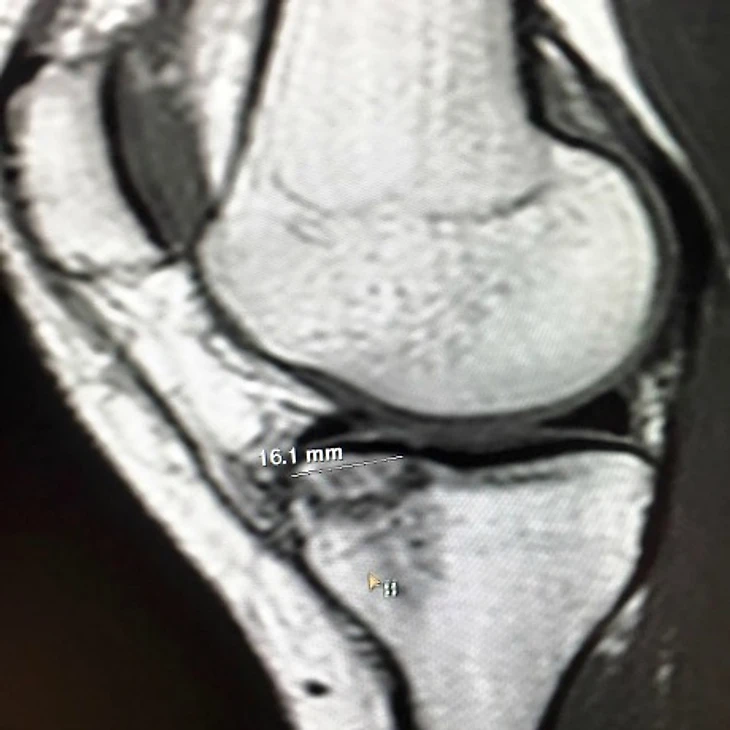

Линдси Вонн: «Томография выявила довольно серьезную трещину в колене»

«Магнитно-резонансная томография выявила довольно серьезную трещину в большеберцовой кости. Внутренняя боковая связка выглядит неплохо, как и остальная часть колена. Теперь буду общаться с тренерами и составлять план», – написала Вонн.